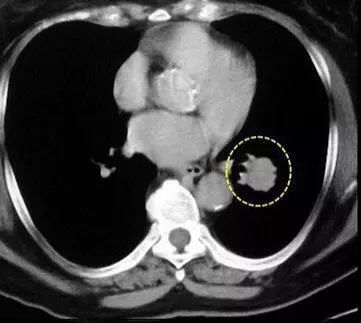

感冒咳嗽长时间不好,或者需要体检,总少不了要做一个肺部的胸片检查,结果有些人拍的片上会发现有一个甚至多个阴影,医生说那是肺部结节。

其实,肺部结节不是疾病的名称,而是拍片所观察到的某些病变的影像学表现的描述。简而言之就是,医生单单只看你肺片里的阴影,是确定不了是什么病的,就用“结节”这个词来描述那些阴影。

虽然说导致肺部结节的,可能是早期肺癌,但也存在很大可能不是肺癌导致的,而要分辨,也很简单,可以结合检查单分析结节的情况,如:

①孤立性肺结节:结节表现清晰,边界清楚,且直径小于3cm,周围被肺组织包绕,无症状。

②若结节为纯毛玻璃样,直接不超过0.8cm,多为不典型腺瘤样增生。由于存在发展的可能,应定期复查。

③若结节直径大于3cm,则为肺肿块,则要考虑肺部肿瘤的可能。